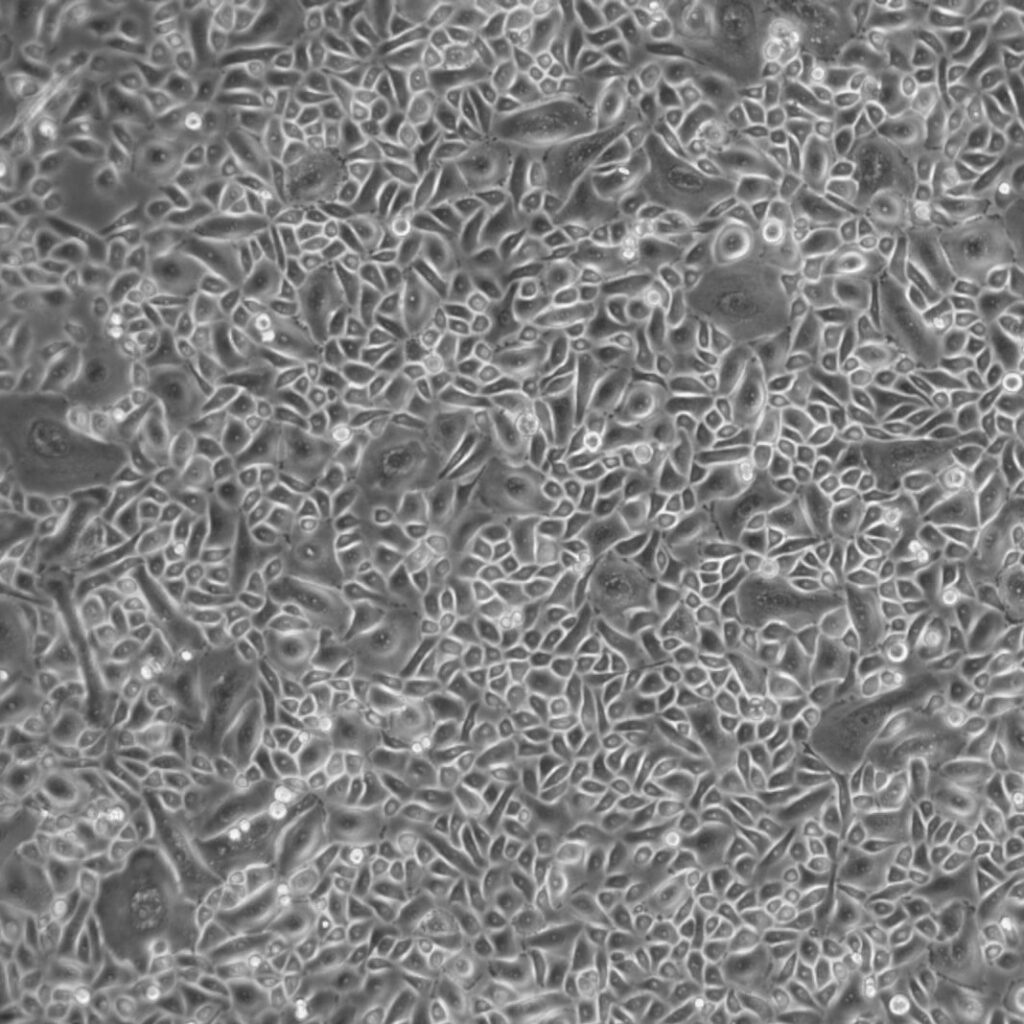

From www.pathologyoutlines.com

Pathology Outlines Bronchiectasis Tracheal Bronchial Bronchiectasis the tracheal bronchus is a rare congenital anomaly described as a collection of bronchial variations arising from the trachea directed. tracheal/bronchial involvement may cause: bronchiectasis is an irreversible widening (dilation) of portions of the breathing tubes or airways (bronchi) resulting from damage to the airway. more common than central airway disease is peripheral bronchial wall thickening. Tracheal Bronchial Bronchiectasis.

From www.lifelinecelltech.com

Primary Bronchial Tracheal Cells with Cystic Fibrosis Tracheal Bronchial Bronchiectasis Bronchiectasis damages your airways, making it hard to clear mucus. bronchiectasis is a chronic lung disease characterized by persistent and lifelong widening of the bronchial airways and weakening of. tracheal/bronchial involvement may cause: more common than central airway disease is peripheral bronchial wall thickening and bronchiectasis, as well as. the tracheal bronchus is a rare congenital. Tracheal Bronchial Bronchiectasis.